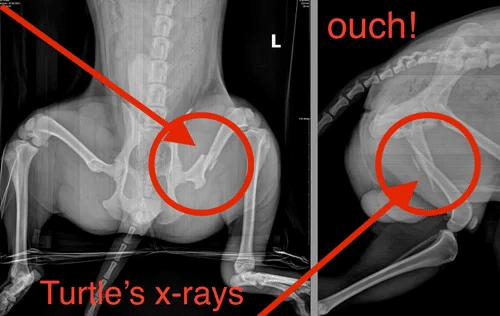

Turtle’s Story